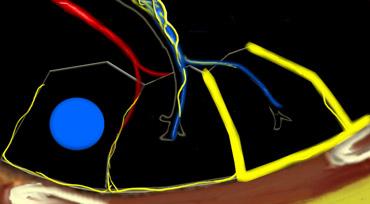

Tiểu thùy thứ cấp. Động mạch trung tiểu thùy (màu xanh lam: máu nghèo oxy) và tiểu phế quản tận cùng đi qua trung tâm. Hệ bạch huyết và tĩnh mạch (màu đỏ: máu giàu oxy) đi trong các vách liên tiểu thùy.

Giải phẫu Tiểu thùy Thứ cấp

Hiểu biết sâu sắc về giải phẫu phổi là yếu tố then chốt để đọc HRCT chính xác. Chẩn đoán các bệnh phổi kẽ (ILDs) dựa trên việc xác định mức độ tổn thương đặc hiệu của tiểu thùy phổi thứ cấp — đơn vị giải phẫu và chức năng cơ bản của phổi.

Trong điều kiện bình thường, chỉ có một số ít các vách mỏng này có thể nhìn thấy trên HRCT. Hệ bạch huyết của tiểu thùy bao gồm hai mạng lưới:

- Một mạng lưới trung tâm, đi dọc theo bó mạch phế quản hướng về trung tâm tiểu thùy.

- Một mạng lưới ngoại vi, nằm trong các vách liên tiểu thùy và dọc theo màng phổi.

Các Vùng Giải Phẫu Quan Trọng

- Vùng Trung Tiểu Thùy (Centrilobular Area): Phần trung tâm của tiểu thùy thứ cấp, thường bị tổn thương trong các bệnh xâm nhập phổi qua đường thở (ví dụ: viêm phổi quá mẫn, viêm phế quản hô hấp, khí phế thũng trung tiểu thùy).

- Vùng Cạnh Bạch Huyết (Perilymphatic Area): Phần ngoại vi của tiểu thùy thứ cấp, thường bị tổn thương trong các bệnh ảnh hưởng đến hệ bạch huyết hoặc các vách liên tiểu thùy (ví dụ: sarcoidosis, ung thư di căn đường bạch huyết, phù phổi). Các bệnh này cũng có thể liên quan đến mạng lưới bạch huyết trung tâm bao quanh bó mạch phế quản.